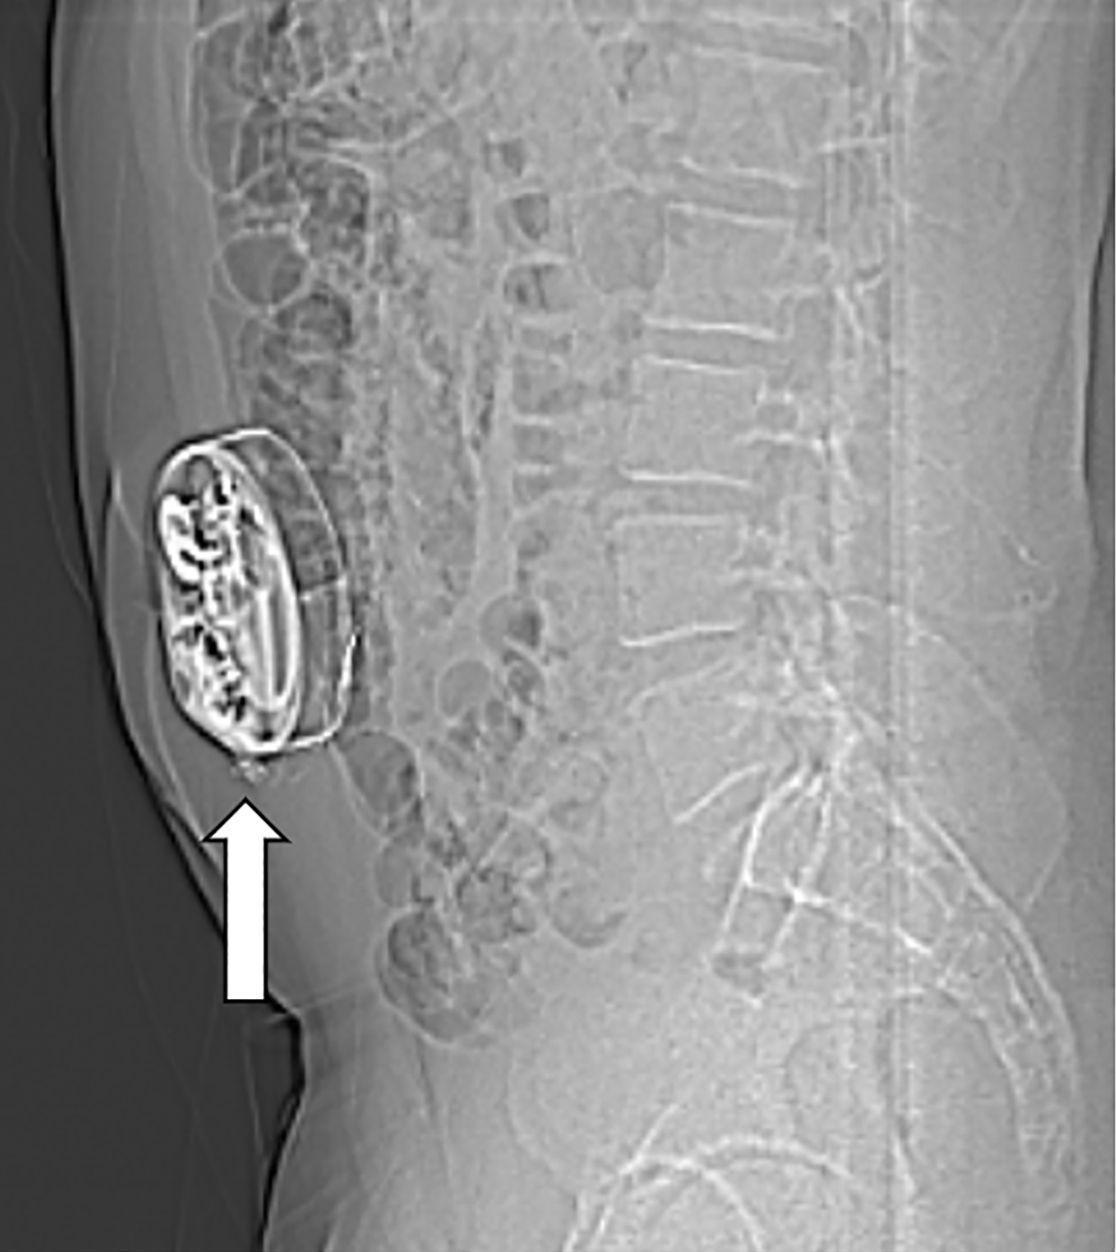

Bei Patienten mit schwerer Spastik oder chronischen Schmerzen, die nicht ausreichend auf herkömmliche medikamentöse Therapien ansprechen, kann die Implantation einer Schmerzpumpe eine effektive Lösung darstellen. Diese Pumpe ermöglicht die direkte Abgabe von Schmerzmitteln oder muskelentspannenden Medikamenten in den Nervenwasserraum (intrathekal), was eine deutlich gezieltere Wirkung mit geringeren Nebenwirkungen ermöglicht als bei in Tablettenform eingenommenen Medikamenten.

Das Pumpensystem besteht aus einem kleinen Schlauch, welcher in den Nervenwasserraum eingebracht wird und mit der Pumpe verbunden ist. Die Pumpe wird meist am Bauch unter der Haut implantiert und ermöglicht, dass die Dosierung der Medikamente exakt an die Bedürfnisse angepasst werden kann. Es ist eine regelmäßige Wiederbefüllung der Pumpe mit den Medikamenten notwendig, was ähnlich wie bei einer Blutabnahme von außen erfolgt.

In unserer Klinik bieten wir Ihnen eine ausführliche Beratung, die Implantation sowie die kontinuierliche Nachsorge dieser Therapie, um Ihre Beschwerden bestmöglich zu lindern und Ihre Lebensqualität zu steigern.

Am Bauch implantierte Medikamentenpumpe (Pfeil)